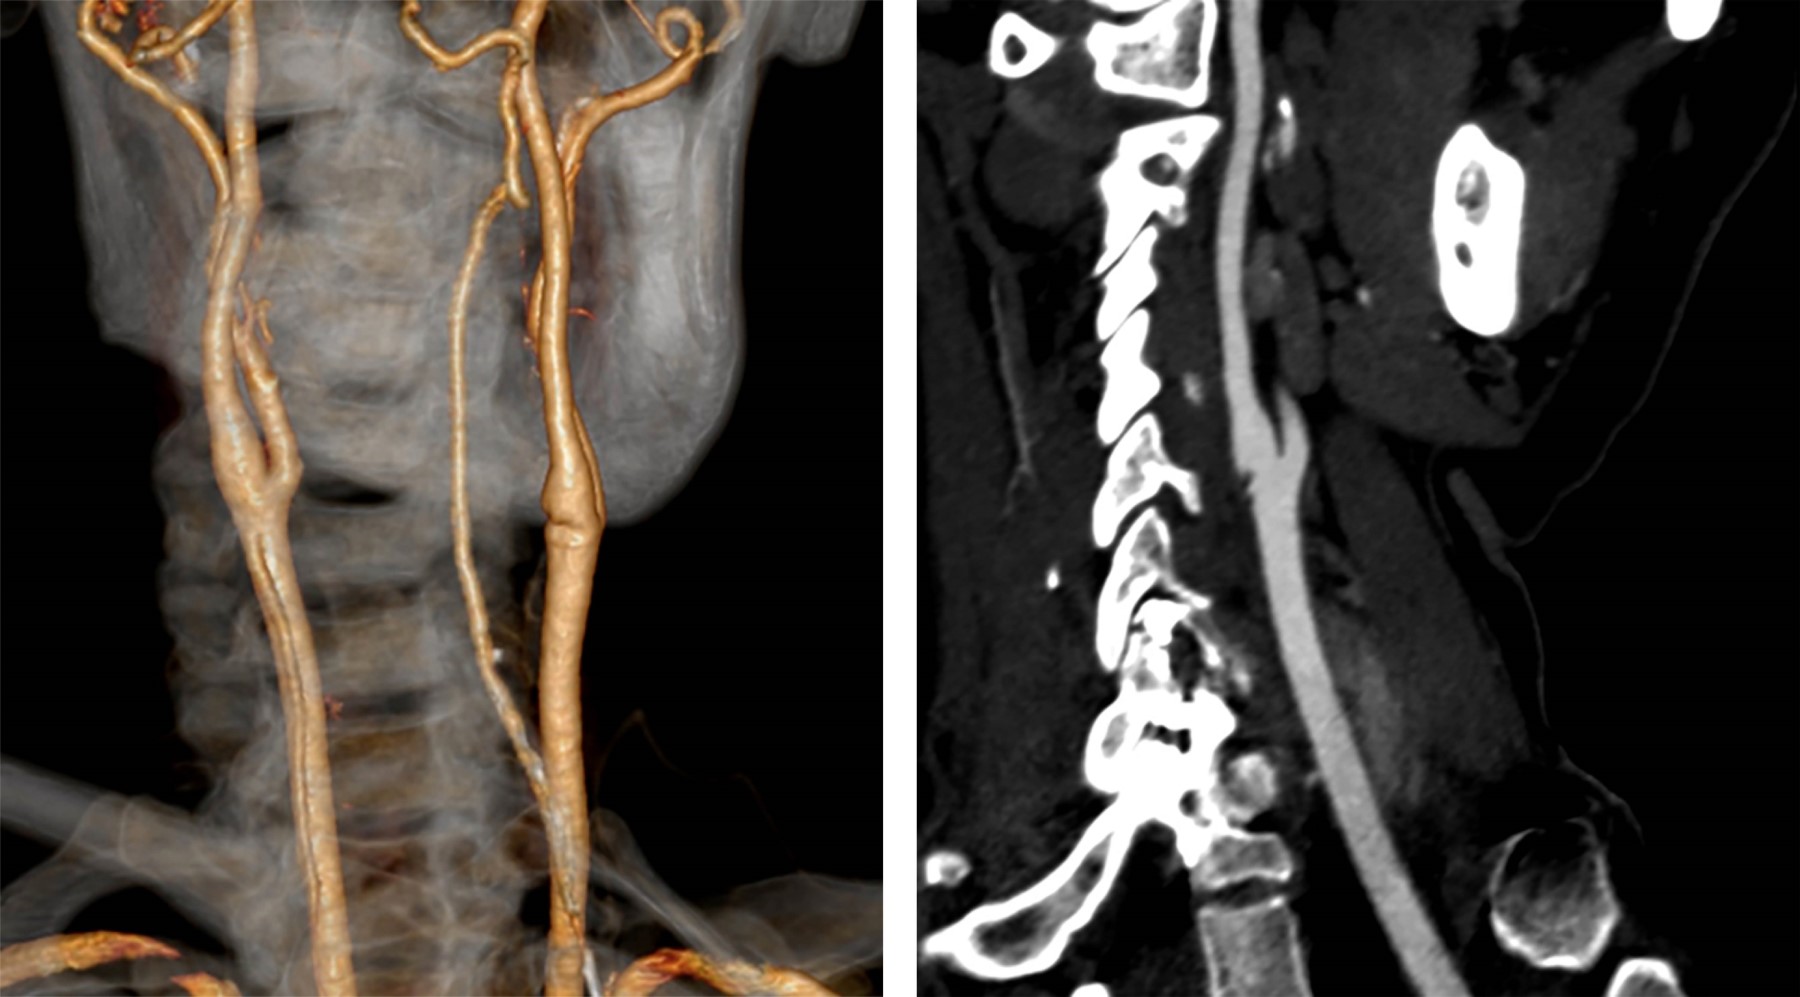

Femenino de 40 años con ataque isquémico transitorio (AIT), en la que se efectuó ultrasonido y angiotomografía que mostraron banda carotídea ipsilateral. La displasia fibromuscular atípica del bulbo o banda carotídea es una patología no ateromatosa implicada en la aparición de infartos cerebrales. La banda carotídea se define como un defecto de llenado lineal en forma de estante en la cara posterior del bulbo de la arteria carótida interna mediante angiotomografía (Figura 1) y/o ultrasonido (Figuras 2 y 3), se reconoce cada vez más como una causa de accidente cerebrovascular criptogénico y/o AIT recurrente, pero la evidencia sigue siendo escasa. Se observa en ambos géneros, con distribución 2:1 a favor del femenino y mayor incidencia en personas de color; cuando son bilaterales (60%) presenta mayor longitud en el lado ipsilateral sintomático que en el contralateral (3-4.5 mm vs 1.85-2.9 mm), observando trombos superpuestos hasta en 30% de los casos con banda carotídea sintomática. A pesar de la recurrencia y gravedad de los accidentes cerebrovasculares originados por embolización asociada con banda carotídea, no existen recomendaciones sobre la mejor estrategia para su manejo; el tratamiento con agentes antiplaquetarios previene la aparición de accidentes cerebrovasculares, pero el tratamiento radical sigue siendo quirúrgico y/o endovascular.

Figura 1